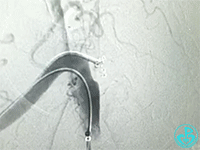

从肱动脉置入8F鞘管,送导丝至“漏口”无法到位,导丝习惯性穿行右胸肩峰动脉中,造影发现血液外溢消失,考虑穿孔口为右胸肩峰动脉远端。接下来送入三个弹簧圈。

最后结果: